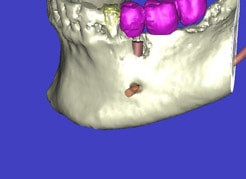

Auf Basis einer computertomografischen (CT-) Kieferaufnahme ist eine dreidimensionale Darstellung der Knochen möglich. Der Zahnarzt kann dann am Computerbildschirm die Knochenqualität (z. B. Knochendichte) beurteilen und die optimale Position der Implantate im Vorfeld planen. Durch Verwendung spezieller Röntgenschablonen lässt sich auch die erwünschte Zahnstellung in die Planung einbeziehen. Die Simulation der OP erlaubt, das zu erwartende Ergebnis mit größtmöglicher Sicherheit vorherzusagen und dem Patienten am Bildschirm zu veranschaulichen.

(siehe Bild 3 und 4).

Mit diesen gewonnenen Informationen und Planungen stellt der Zahnarzt interaktiv spezielle Bohrschablonen her. Diese ermöglichen eine exakte Positionierung der Implantate, so wie vorher am Computer geplant.